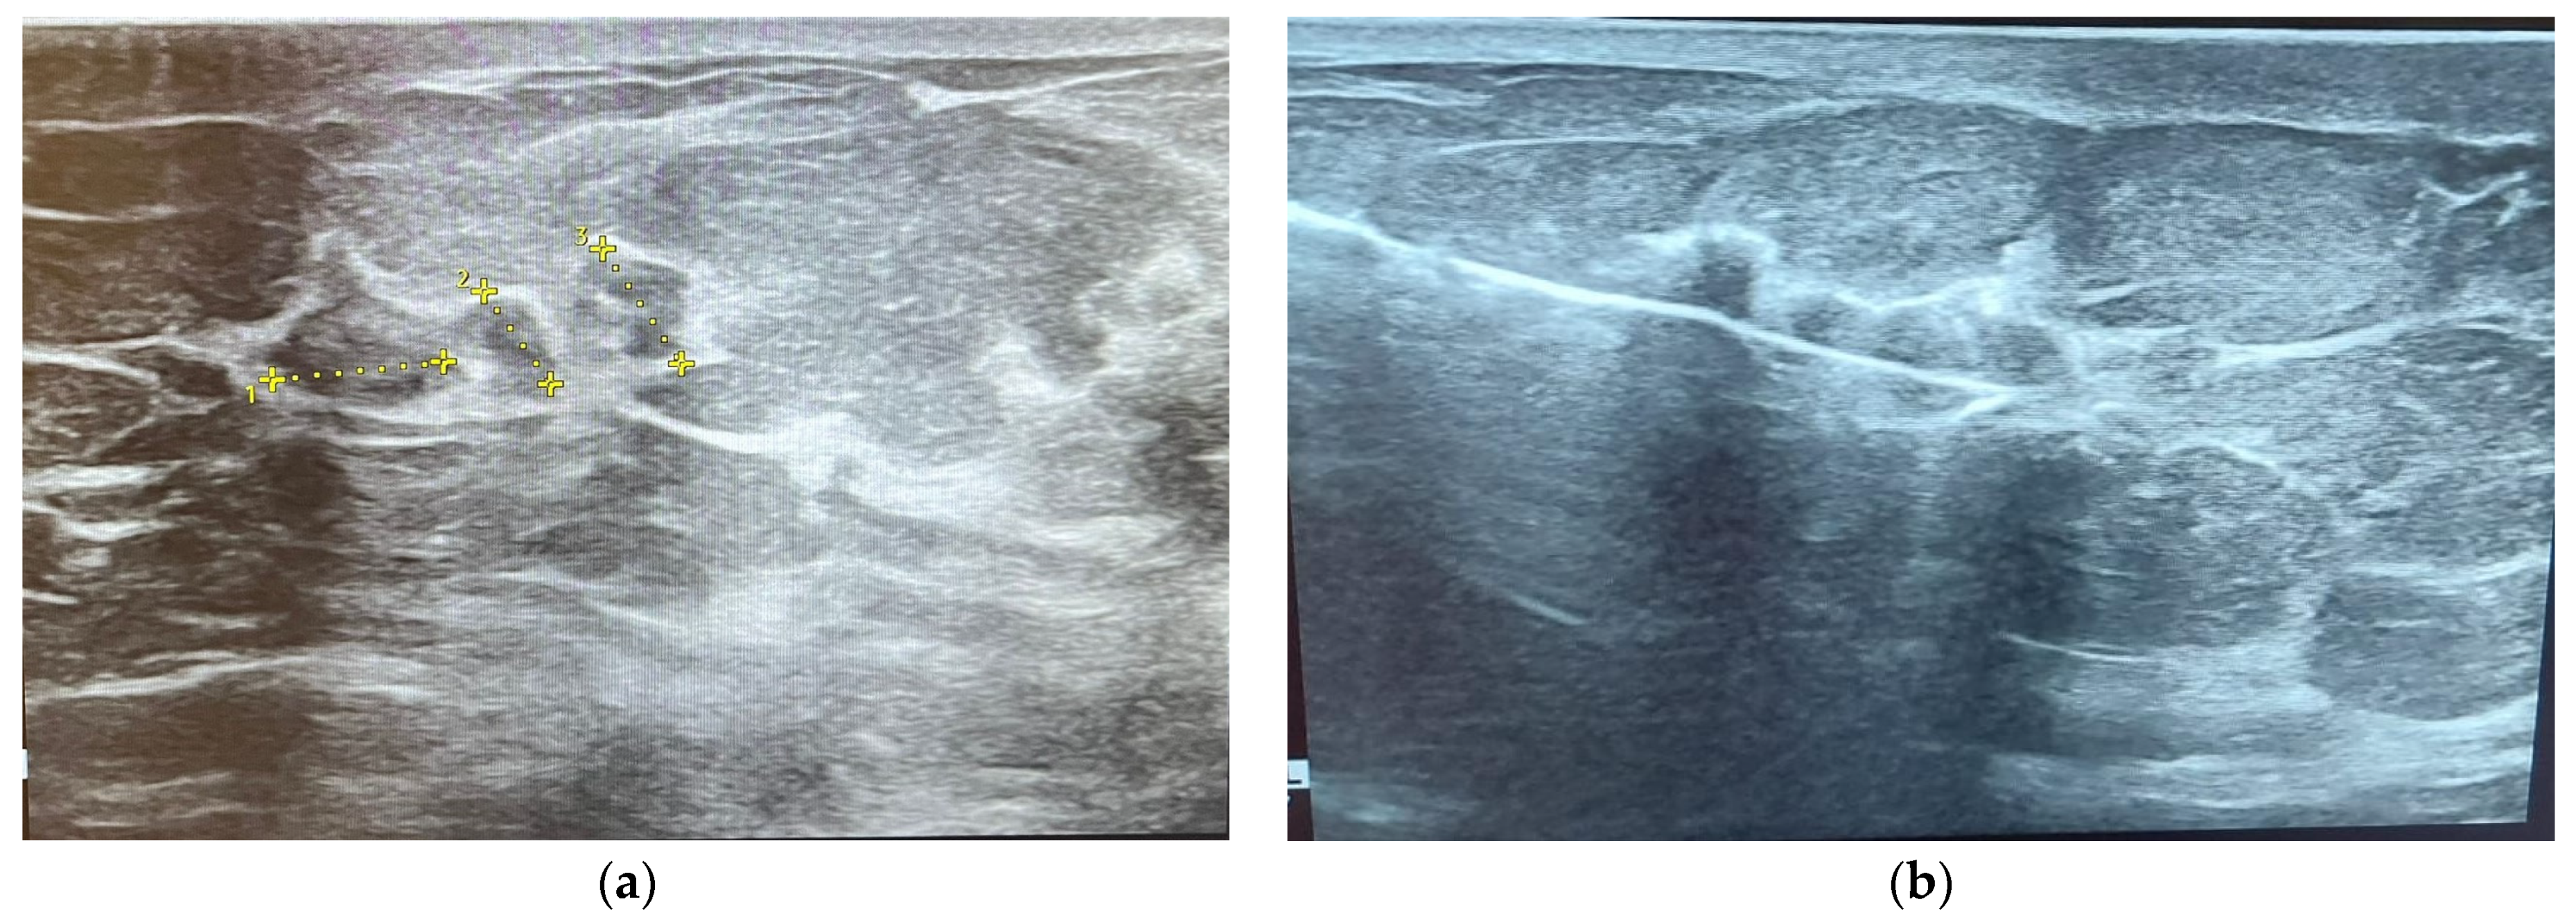

2.3. Ultrasonography (US)

3.6. Correlations between Molecular Subtypes of BC and Their Ultrasonographic Features

- Pan, Q.H.; Zhang, Z.P.; Yan, L.Y.; Jia, N.R.; Ren, X.Y.; Wu, B.K.; Hao, Y.B.; Li, Z.F. Association between ultrasound BI-RADS signs and molecular typing of invasive breast cancer. Front. Oncol. 2023, 13, 1110796. [Google Scholar] [CrossRef] [PubMed]

- Liang, X.; Li, Z.; Zhang, L.; Wang, D.; Tian, J. Application of Contrast-Enhanced Ultrasound in the Differential Diagnosis of Different Molecular Subtypes of Breast Cancer. Ultrason. Imaging 2020, 42, 261–270. [Google Scholar] [CrossRef]

- Rashmi, S.; Kamala, S.; Murthy, S.S.; Kotha, S.; Rao, Y.S.; Chaudhary, K.V. Predicting the molecular subtype of breast cancer based on mammography and ultrasound findings. Indian. J. Radiol. Imaging 2018, 28, 354–361. [Google Scholar] [CrossRef] [PubMed]

- Zhu, J.Y.; He, H.L.; Jiang, X.C.; Bao, H.W.; Chen, F. Multimodal ultrasound features of breast cancers: Correlation with molecular subtypes. BMC Med. Imaging 2023, 23, 57. [Google Scholar] [CrossRef]